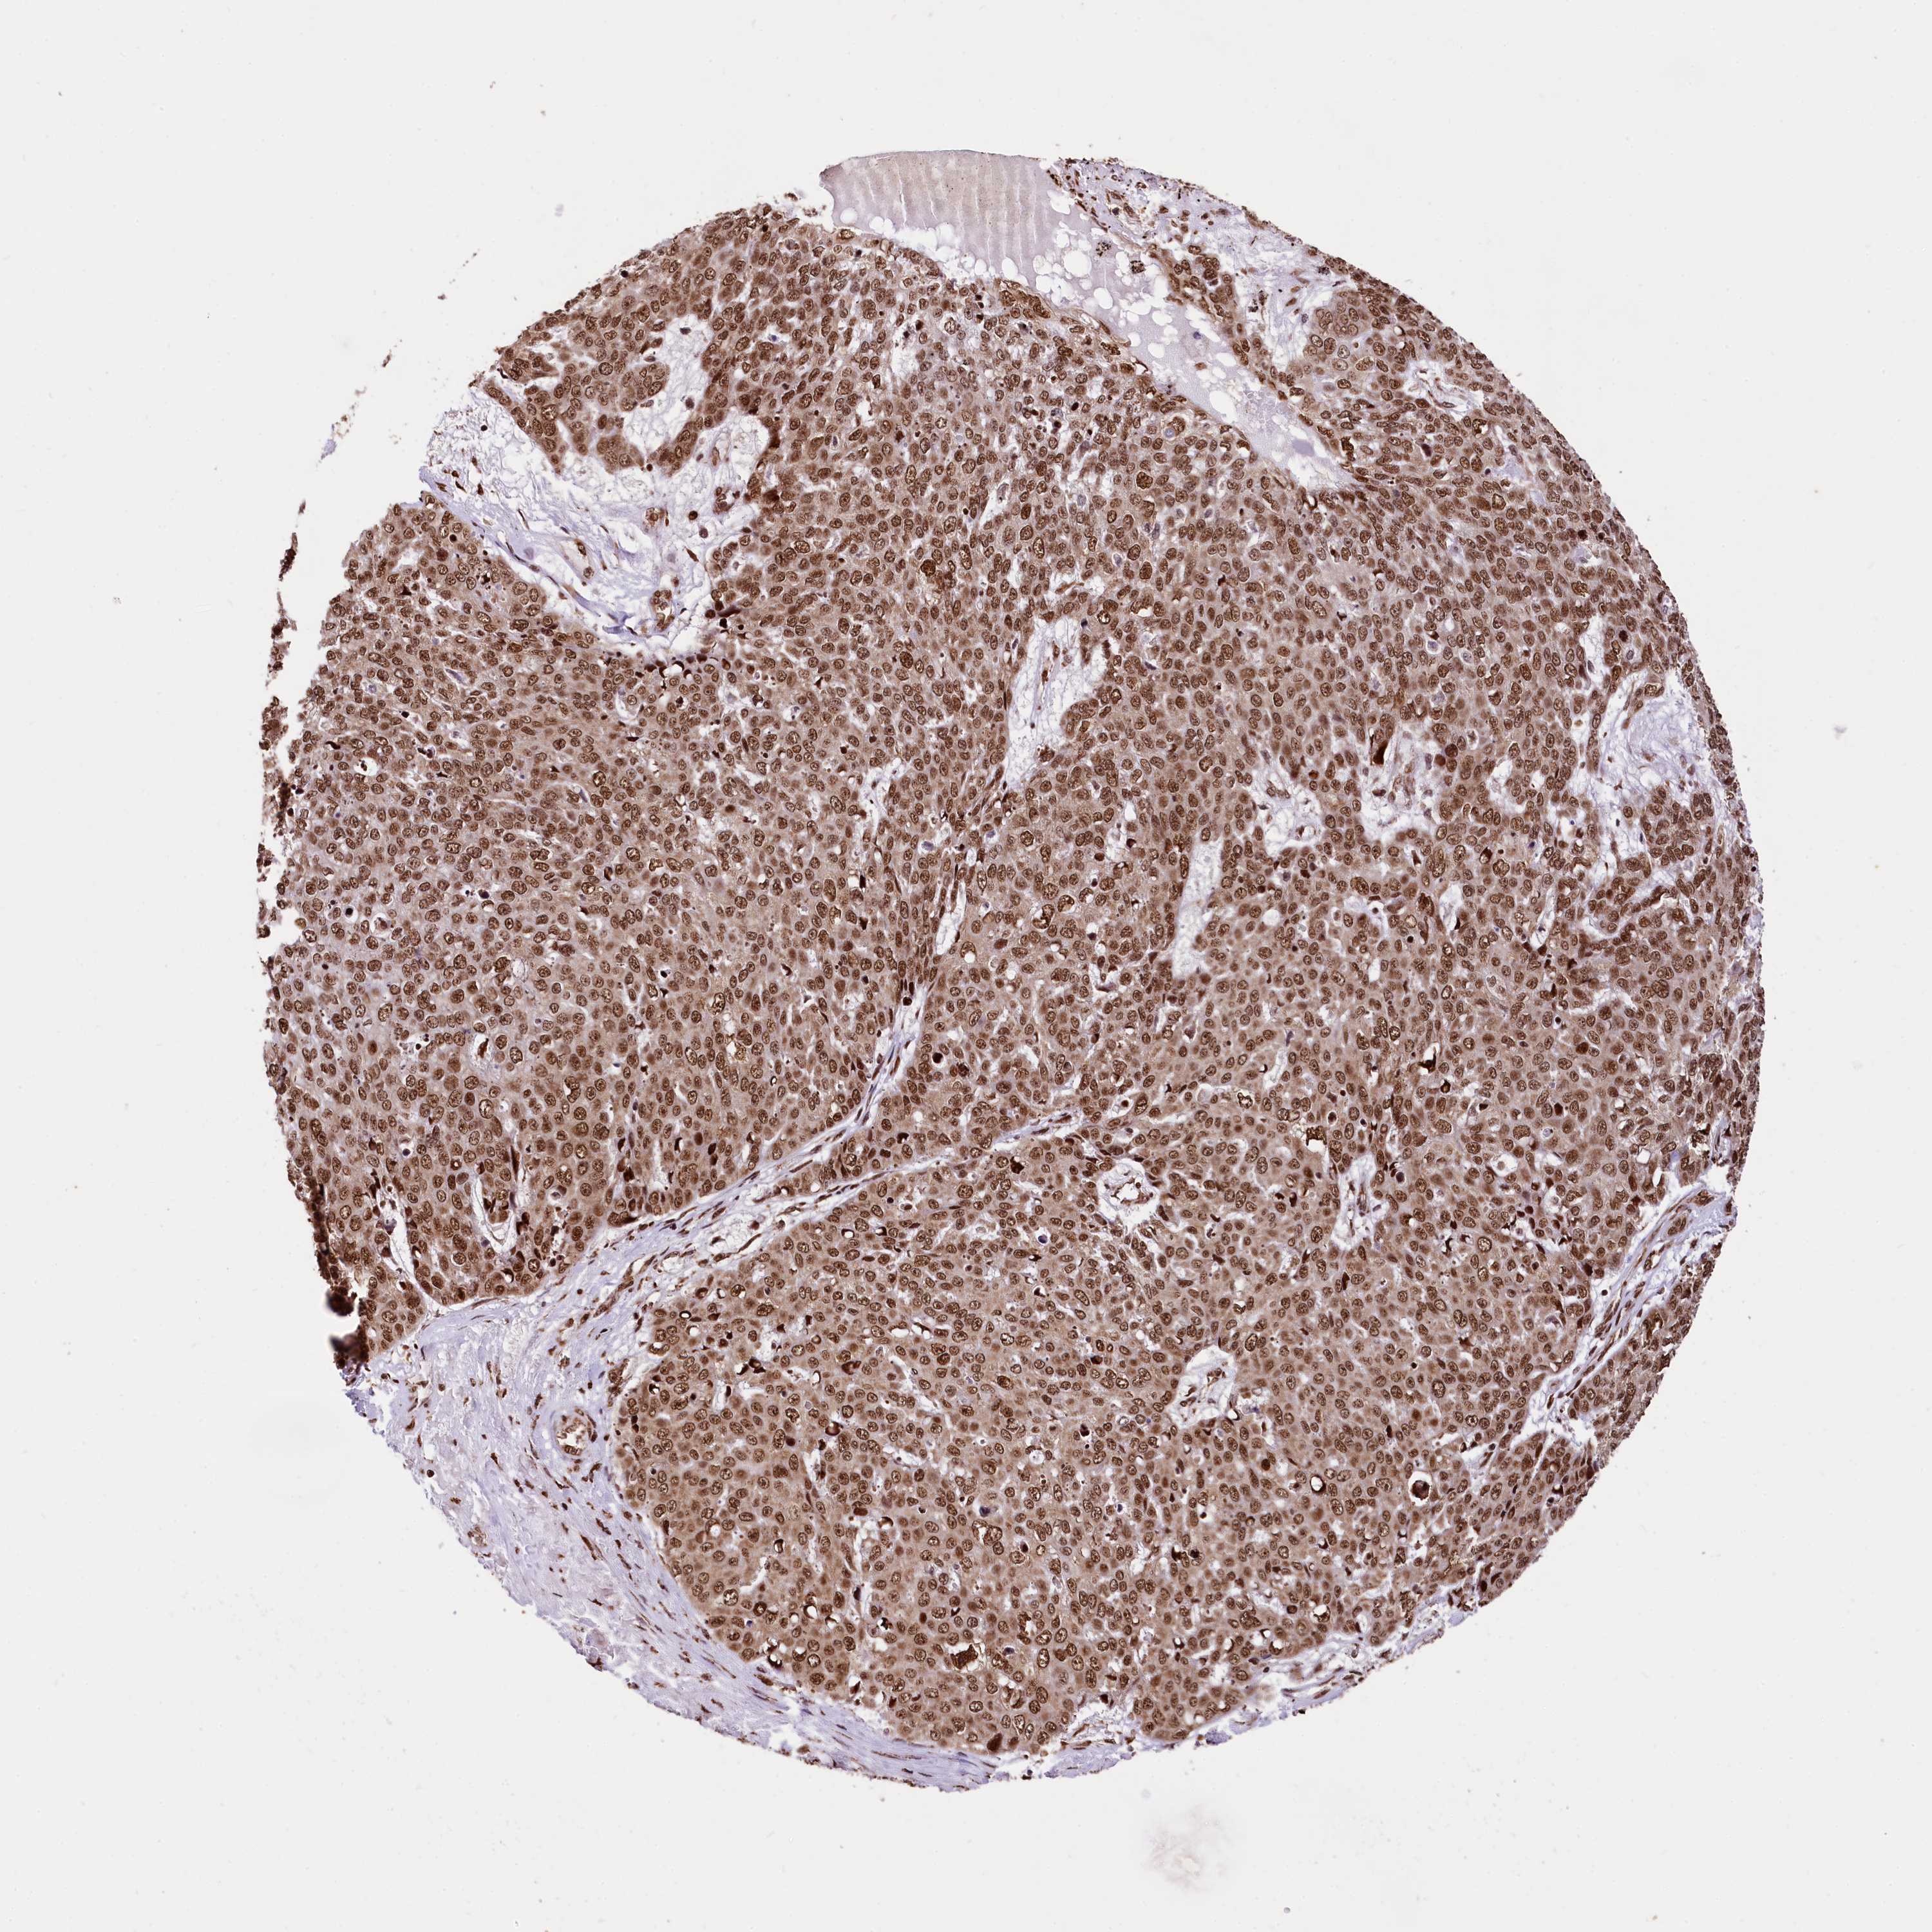

SKIN CANCER - Protein expressioni

A mouse-over function shows sample information and annotation data. Click on an image to view it in a full screen mode. Samples can be filtered based on level of antibody staining by selecting one or several of the following categories: high, medium, low and not detected. The assay and annotation is described here.

Antibody stainingi

Antibody staining in the annotated cell types in the current human tissue is reported as not detected, low, medium, or high, based on conventional immunohistochemistry profiling in selected tissues. This score is based on the combination of the staining intensity and fraction of stained cells.

Each image is clickable and will lead to virtual microscopy that enables deeper exploration of all samples and also displays staining intensity scores, fraction scores and subcellular localization as well as patient and tissue information for each sample.

Antibody HPA039513

Antibody HPA040015

Staining

High

Medium

Low

Not detected

Intensity

Strong

Moderate

Weak

Negative

Quantity

>75%

75%-25%

<25%

None

Location

Nuclear

Cytoplasmic/membranous

Cytoplasmic/membranous,nuclear

Basal cell carcinoma

Squamous cell carcinoma, NOS

Squamous cell carcinoma, metastatic, NOS